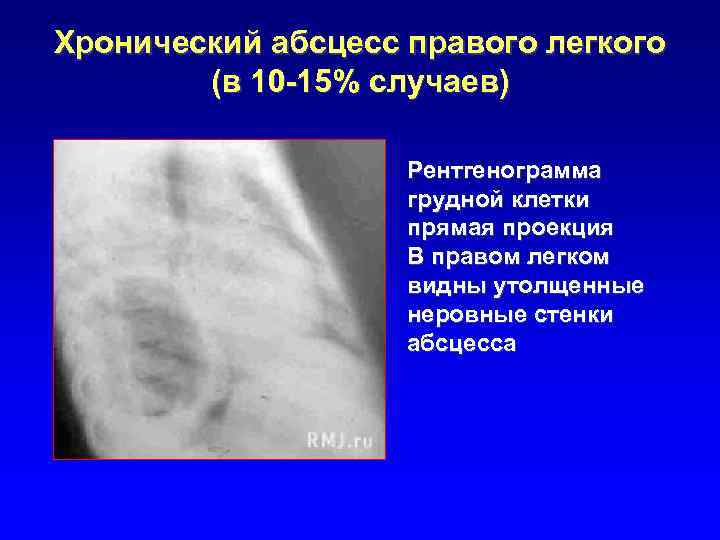

Хронический абсцесс правого легкого (в 10 -15% случаев) Рентгенограмма грудной клетки прямая проекция В правом легком видны утолщенные неровные стенки абсцесса